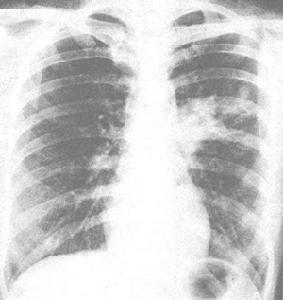

X線檢查早期肺紋理增多,模糊,病程4-5日可出現大小不等片狀病灶,以兩肺下野和右上肺多見,病後6-11日病灶增多,分布較廣,互相融合,呈大片浸潤狀,但不局限於某葉,可有一側胸腔積液。

小兒急性肺炎X線檢查主要示間質性肺炎、肺氣腫及肺泡病變,多為小點片狀陰影,少數呈塊狀陰影,可融合,邊緣模糊不清。肺野外帶透明度增高,可伴局部肺不張或局限性肺氣腫。

主要依據咳嗽、發熱、氣促、肺部細濕羅音等臨床表現,再結合胸部X線片可明確肺炎的診斷。